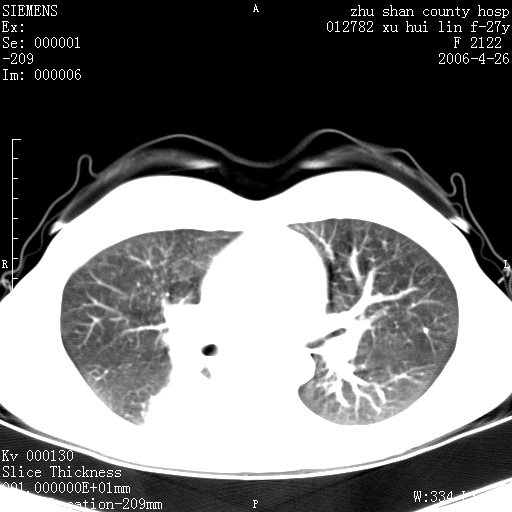

女性 病人 27岁!本院职工家属,五月前因感冒透视发现病变,ct示:左肺下叶背段感染性病变。经过半月规范抗生素治疗后复查病变无明显变化,后行四月规范抗痨治疗,复查无明显变化,后复查无效!请大家帮忙看看!

右肺下叶背段见片状高密度区,边界不清,密度不均,无钙化及空洞影,背段支气管通畅。所见层面肺门及纵隔内未见明显肿大淋巴结影。

女性 病人 27岁!本院职工家属,五月前因感冒透视发现病变,ct示:左肺下叶背段感染性病变。经过半月规范抗生素治疗后复查病变无明显变化,后行四月规范抗痨治疗,复查无明显变化,后复查无效!

诊断:首先还是考虑为慢性炎症。

结核虽然好发于下叶背段,但周围无明显卫星灶,化验结果怎样?